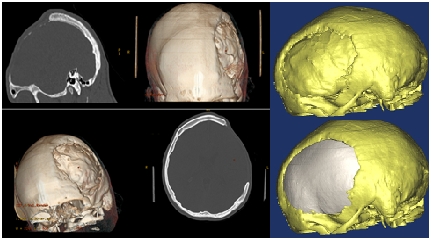

Godine 2018., na Odjelu neurohirurgije Kantonalne bolnice Zenica, urađena je prva 3D rekonstrukcija velikog i kompleksnog defekta lobanje. Od te operacije je prošlo 5 godina. Pacijent se potpuno oporavio i vratio normalnim životnim i radnim aktivnostima. Naravno, tim Odjela neurohirurgije je ovu proceduru uveo kao standard prilikom zatvaranja velikih defekata na kostima lobanje, kako bi se dobio maksimalan estetski i funkcionalni rezultat.Sama metoda je već prezentirana kao inovativna i objavljena u relevantnom časopisu.

Prije dvije sedmice, na Odjelu neurohirurgije, urađena je još jedna, do sada najkompleksnija 3D rekonstrukcija lobanje. Projekat su realizirali doc.dr. Hakija Bečulić, dr. Anes Mašović i diplomirani inžinjer mašinstva mr.sci. Denis Spahić.

Radi se o devetnaestogodišnjem pacijentu iz Konjica, koji je dvije godine ranije preživio tešku povredu glave iza koje je zaostao veliki defekt svih kostiju lijeve polovine lobanje, uključujući dio baze lobanje i zida očne duplje. Primjenom standarnih metoda u neurohirurgiji i estetskoj hirurgiji nije bilo moguće uraditi vjerodostojnu estetsku i funkcionalnu rekonstrukciju lobanje.

Ponovno se pokazalo da tehnologija i medicina idu rame uz rame. Na osnovu 3D kompjuterizirane tomografije glave napravljen je 3D model lobanje pacijenta, koji je poslužio za formiranje originalnog transplantata.Kalup za transplantat je napravljen na 3D printeru i milimetarski je odgovarao defektu kojeg je trebalo zatvoriti.Sama rekonstrukcija je uspješno realizirana i dobijen je maksimalan estetski i funkcionalni rezultat. U odnosu na ranije rekonstrukcije ova je bila mnogo kompleksnija i tehnički najzahtjevnija, posebno zbog rekonstrukcije bazalnog i prednjeg dijela lobanje, što samo po sebi, značajno produžava trajanje operacije.

Posebno ističemo da je sama metoda inovativna i u cijelosti je, u jako skromnim materijalnim uslovima, uvedena i realizirana u Zenici.

Napominjemo da je korištenje 3D tehnologije za veće rekonstruktivne zahvate na glavi postao standard na Odjelu neurohirurgije. Iskreno se nadamo da će ovakve i slične inovativne ideje biti okosnica razvoja naše ustanove.